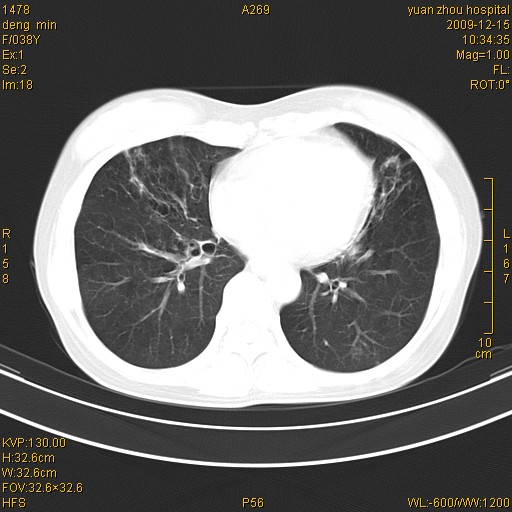

标题: CT23919:F38Y 咳嗽月余 [打印本页]

标题: CT23919:F38Y 咳嗽月余

支气管扩张。典型。

右肺中下叶、左肺上叶舌段及左肺下叶支气管扩张合并感染。